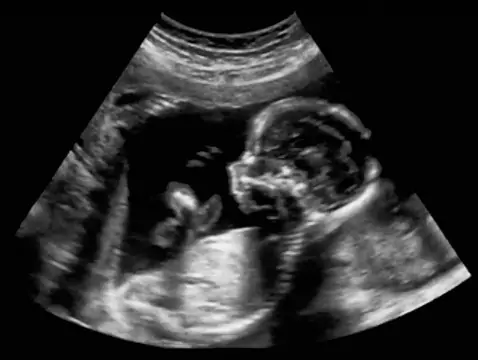

O tym, czym jest, kiedy należy je wykonywać oraz jakich informacji możemy oczekiwać po badaniu USG połówkowym, dowiesz się z tego artykułu.

Badania prenatalne od dawna odgrywały istotną rolą w ginekologii i położnictwie, współcześnie jednak ich wartość stale się zwiększa z powodu tego, że coraz więcej kobiet późno zachodzi w ciążę. Wśród...

W ciąży konieczne jest wykonywanie wielu różnych badań, których celem jest ocena stanu zdrowia zarówno przyszłej mamy, jak i jej dziecka. Jakie badania w ciąży są obowiązkowe i kiedy wykonuje się...